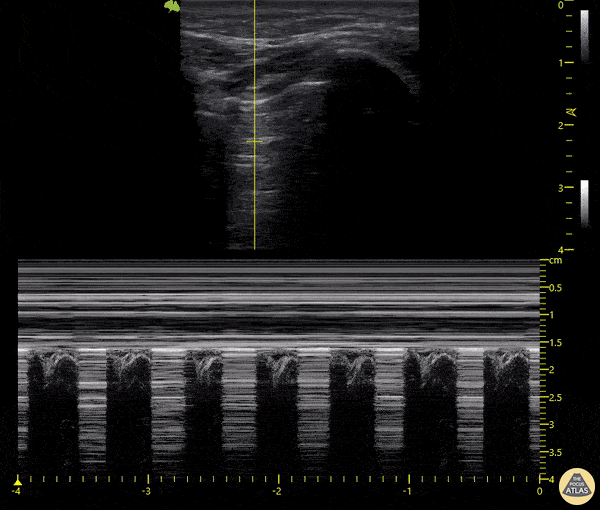

Pulmonary - Lung Point

18-year-old patient who presented following a motorcycle accident in which he sustained closed chest trauma with bilateral hemopneumothoraces. In this sequence taken with a linear transducer in left pulmonary zone 1, the "pulmonary point" indicative of pneumothorax can be seen. Libardo Valencia Chicue